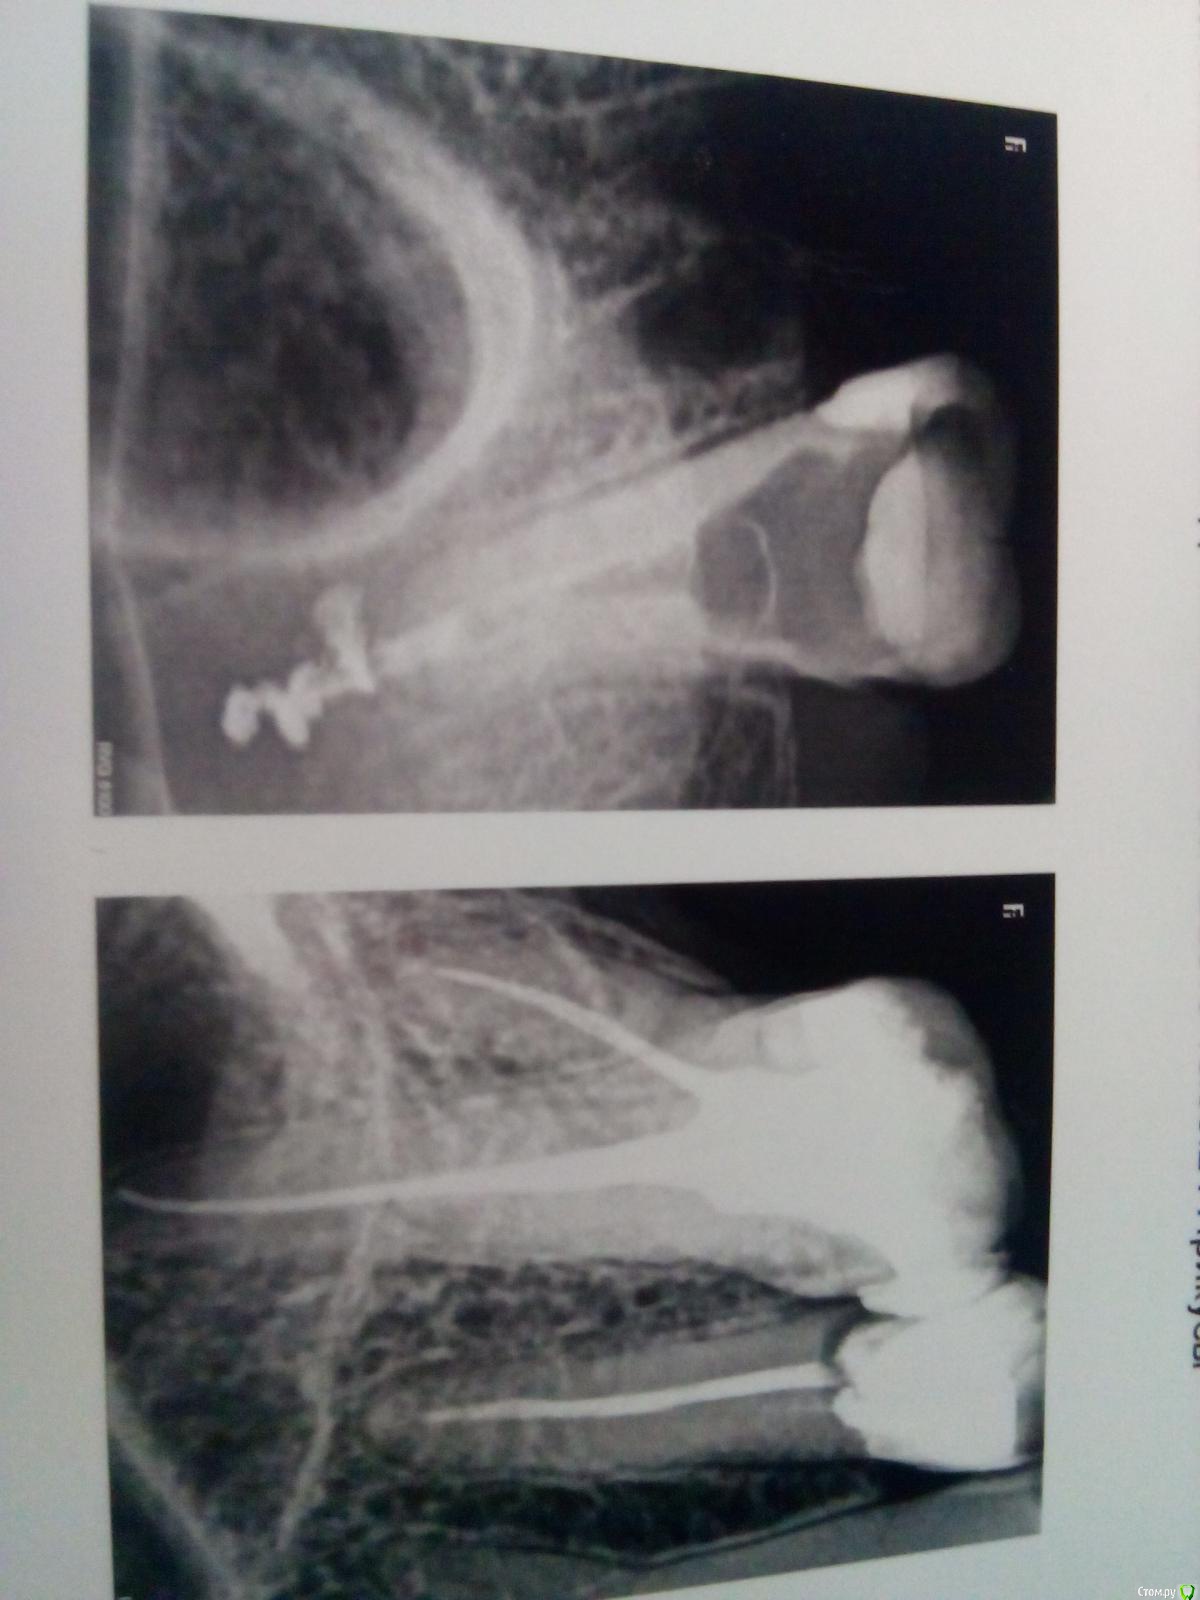

Musya31 Опубликовано 29 декабря, 2015 Поделиться Опубликовано 29 декабря, 2015 Добрый день!Врач ввел в каналы метапекс на месяц. Так удачно, что на снимке видно, как за каналами целая лужа растеклась. Корни выходят в гайморову. А она у меня в принципе и так нездорова. Врач сказал - ничего страшного - за месяц все рассосется. Это было 5 дней назад. Все это время страшная тошнота до рвоты, головокружение, постоянный вкус йода во рту. Вопрос такой: правда ли ничего страшного и лекарство действительно рассосется? И может ли быть такая реакция на лекарство? У меня аутоимунный тиреодит и я теперь вообще в шоке, что делать? Ведь если из каналов его можно как-то вымыть, то из гайморовой никак? Сильно ли все это повредит здоровью, щитовидке? Ссылка на комментарий

Musya31 Опубликовано 30 декабря, 2015 Автор Поделиться Опубликовано 30 декабря, 2015 Прикрепляю снимки. Там еще снимок 5-ки с другой стороны. Боль в 6 (с выведеным материалом) сильная, распирающая, постоянная. И чем-то похоже, как у меня карман в 5-ке ссоседней стороны болит или как на десне - рана. Вая сегодня посмотрела. говорит не отека, ни покраснений. Терпеть. Мне ее перелечивают уже 3-й раз. 6-ку соседнюю удалили 2 месяца назад - думали в ней дело. Потом обнаружили, что в 7-ке карман со стороны 8-ки большой и в нем дыра в корень уходящая. Вот перелечивают опять. Вот еще ссылка на КТ - вас не затруднит посмотреть, что ж там на самом деле может болеть? Врачи что-то со стороны 8-го давным давно удаленного зуба увидели, но не поняли что. КТ https://cloud.mail.ru/public/JCvH/W67WtQ8uEМожет в этой 7-ке не два канала, а больше? Но два врача смотрели. говорят, нет два. Извините за сумбур - но измучилась капитально просто. А завтра новый годСамое интересное, что обезболивающие не помогают.... Ссылка на комментарий

Musya31 Опубликовано 30 декабря, 2015 Автор Поделиться Опубликовано 30 декабря, 2015 Забыла снимок прикрепить - вот он... Ссылка на комментарий

Musya31 Опубликовано 30 декабря, 2015 Автор Поделиться Опубликовано 30 декабря, 2015 Уф. Наконец получилось... Ссылка на комментарий